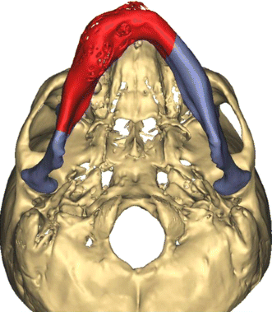

At present, mandibular reconstruction with a fibular free flap is the gold standard for functional and esthetic rehabilitation after oncological surgery. The purpose of this study was to describe the computer-assisted mandibular reconstruction procedure adopting the customized solution Synthes ProPlan CMF. The study reports five consecutive patients with benign or malignant disease requiring mandibular reconstruction using a microvascular fibular free flap, pre-operative virtual planning, construction of cutting guides and customized laser pre-bent titanium plates. The surgical technique is discussed in a step-by-step fashion. The average post-operative hospital stay was 18 ± 3 days. Ischemia time was recorded in all five cases, with an average of 75 ± 8 min. No problems were encountered in any surgical step and there were no major complications. Excellent precision of cutting guides and a good fit of pre-bent plates were found on both the mandible and fibula. There was excellent precision in bone to bone contact and position between mandible and fibula graft. Measurement data from the pre-operative and post-operative CT scans were compared. The average difference (Δ) between programed segment lengths and CT control segment lengths was 0.098 ± 0.077 cm. Microsurgical mandibular reconstruction using a virtual surgical planning yields significantly shorter ischemia times and allows more precise osteotomies. The technology is becoming increasingly recognized for its ability to optimize surgical outcomes and minimize operating time. Considering that the extent of resection can be wider than predicted, this results in safer modeling of the fibula only after frozen sections have demonstrated the radicality of resection.